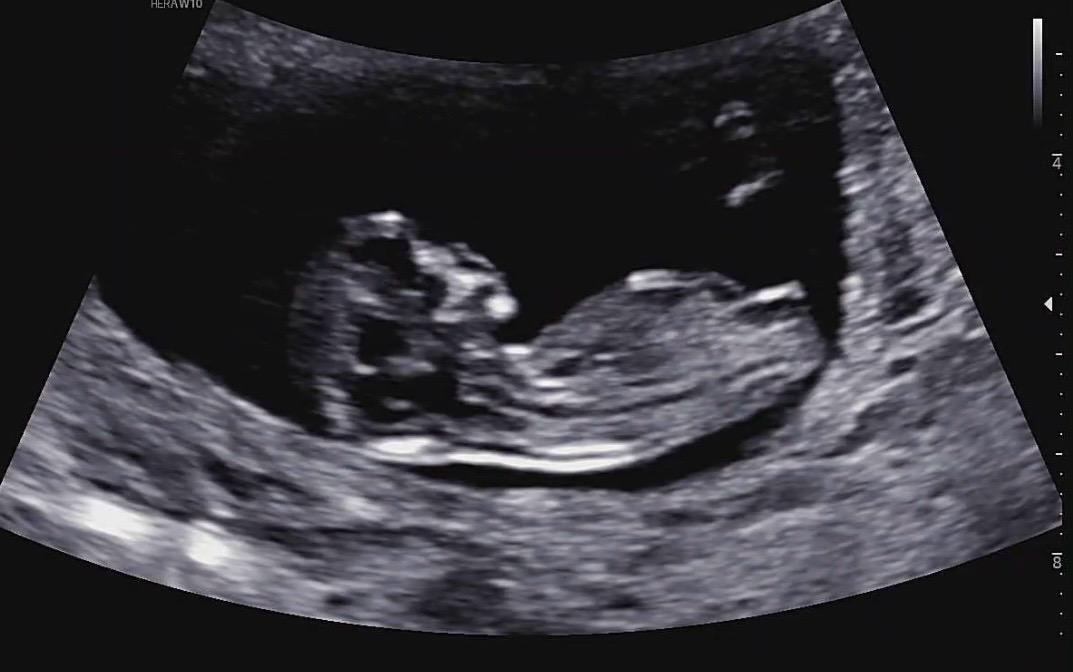

저도 각도법 한번 봐주실수 있을까요🥹

각도법 저희는 봐도봐도 모르겠어서ㅠㅠ 딸일까요 아들일까요..?

딸에 한표요!